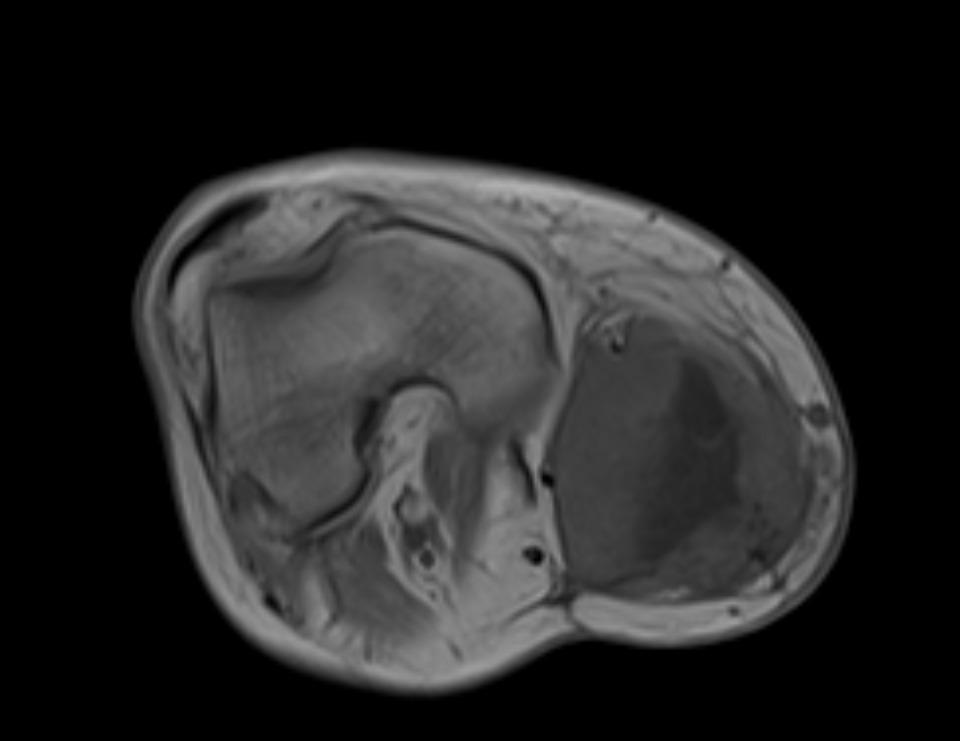

Healthy Eye

Blast Eye